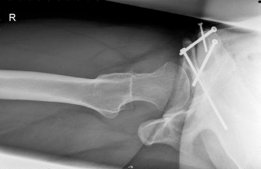

With the acetabular fragment now mobile, a 5.0mm Schanz pin is placed into the supra-acetabular region to act as a joystick. The fragment is mobilized and rotated laterally and anteriorly to achieve the pre-planned coverage. We also intentionally medialize the fragment to optimize the abductor lever arm. The hip is taken through a full range of motion to ensure there is no iatrogenic anterior impingement. Fluoroscopy is utilized extensively at this stage. We obtain AP, false profile, and obturator oblique views to confirm the correction of the LCEA, ACEA, and Shenton's line, and to ensure the joint space remains perfectly congruent.

Once the optimal position is achieved and verified, provisional fixation is obtained with Kirschner wires. Definitive fixation is then achieved using three or four fully threaded 4.5mm cortical screws directed from the intact ilium down into the acetabular fragment. The screws must be carefully placed to avoid intra-articular penetration. After final fluoroscopic confirmation, the rectus femoris is reattached to the AIIS, and the wound is closed in layers over a deep subfascial drain. The skin is closed with a subcuticular suture to optimize the cosmetic outcome for this young patient.